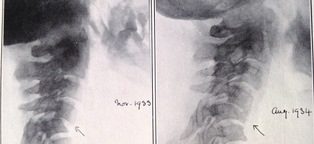

By the 1920s, radiology was becoming recognised as a distinct medical speciality. In the 1930s there was a gradual standardisation of projections which culminated in the publication of Positioning in Radiography by Kitty Clark in 1939, which remains in print today.

It was all about the position. We could see if there was something wrong with my head if I put it in the same position as yours.

He writes a book on neuroradiology. How to x-ray the brain. He publishes it twice. By the time the second edition emerges it is already nearly out of date. The CT scan and MRI are developing quickly and so much of his research is obsolete.